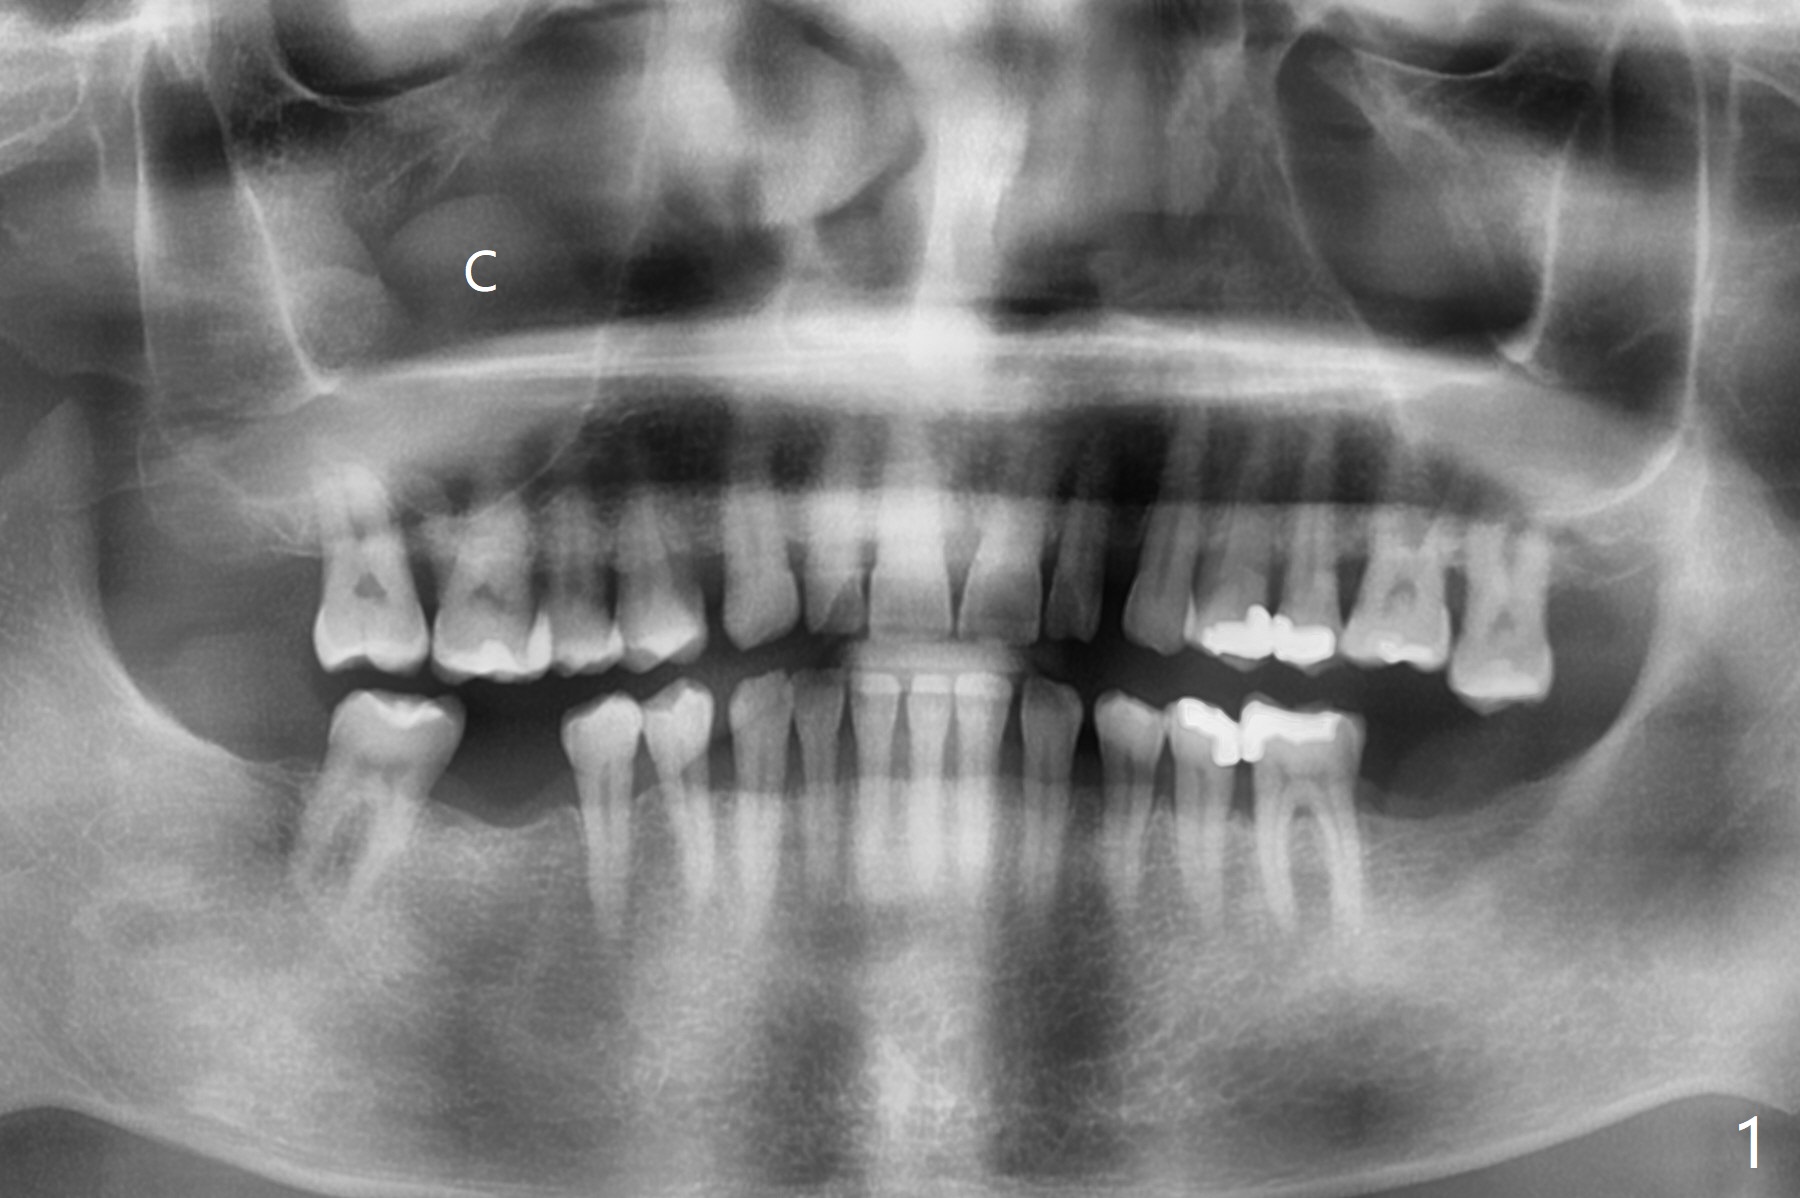

A 56-year-old man (smoker) has pain at #2 (Fig.1-3 thickened sinus membrane (R>L), C: mucous retention cyst) associated with subgingival crack (Fig.4 arrowheads). A 5x8.5 mm implant will be immediately placed with sinus lift aided by PRF membrane (Fig.5). A narrow implant will be placed at #30 (Fig.6).